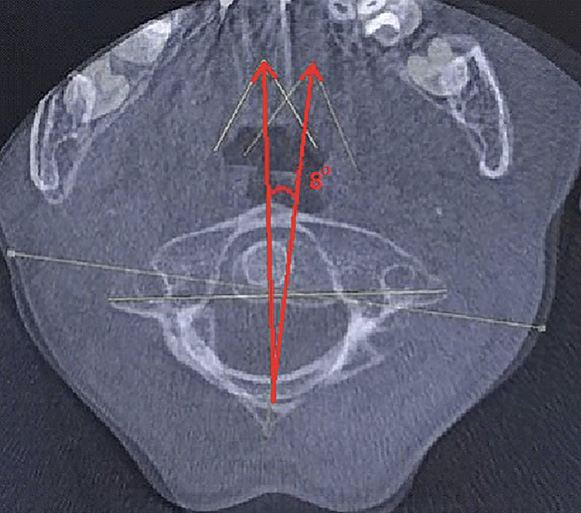

Пациент В. 9 лет обратился с жалобами на боли и вынужденное положение головы в виде наклона вправо. Из анамнеза, со слов матери, данное состояние возникло на фоне проведенной эндоскопической аденотомии и тимпаноскопии справа около 3 недель назад. На 2-е сутки после проведенного вмешательства, со слов матери, у ребенка появилось вынужденное положение головы в виде наклона вправо и постоянные боли постепенного нарастающего характера по боковой поверхности шеи справа. По данному поводу спустя 7 дней мальчик был консультирован у оперирующего хирурга, который расценил данную ситуацию как допустимые изменения послеоперационного характера. В связи с отсутствием очевидных улучшений мать ребенка приняла решение о необходимости обращения к врачу травматологу-ортопеду. При первичном осмотре ребенка отмечался вынужденный наклон головы вправо до угла в 54°, боли при пальпации по боковой поверхности шеи справа (6-7 баллов по Визуально-аналоговой шкале). Пассивные движения в шейном отделе позвоночника были представлены безболезненным наклоном вперед в пределах 10°, наклоном назад в пределах 3°, наклонами вправо и влево в пределах 5°. Активные движения в шейном отделе позвоночника были представлены в виде безболезненного наклона вперед в пределах 15°, назад в пределах 5-7°, наклонов вправо и влево в пределах 7–10 градусов. Превышение представленных объемов пассивных и активных движений вызывало усиление болей, ротационные движения осуществить не удалось. По остальным отделам костно-мышечной системы отклонения не выявлены. С учетом клинической картины было принято решение выполнить КЛКТ, по результатам которой зафиксировано следующее: ротация атланта вправо вокруг вертикальной оси без передней дислокации. Рентгеновская щель срединного атлантоаксиального сустава не расширена, равна 2,5 мм, что соответствует возрастной норме. Суставные рентгеновские щели латеральных атлантоаксиальных суставов асимметричны: справа 3,1 мм, слева 1,5 мм. Расстояние между медиальными краями боковых масс атланта и зубом аксиса: справа – 2,4 мм, слева – 8,9 мм (рис. 1). Определяется боковое смещение атланта влево: нижняя суставная поверхность левой боковой массы атланта смещена на 4,5 мм влево относительно суставной поверхности аксиса.

Рис. 1. Конусно-лучевая компьютерная томография краниовертебральной области, фронтальный срез на уровне зубовидного отростка С2 позвонка. Методика измерения соотношений в латеральных атланто-аксиальных суставах